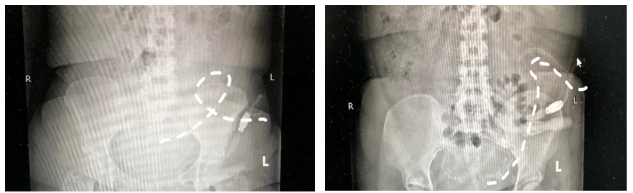

60岁的老李是一位刚刚开始腹膜透析的肾友,最近给腹透中心的医务人员打来电话说,平时超滤有200多,最近开始出现了负数,近期体重开始增加。接到电话,医务人员把老李约到门诊,仔细询问之下,发现他透析后食欲明显增加,很爱吃肉,不爱吃蔬菜,排便约3天一次,质偏干,平时不爱运动。在立卧位腹平片的检查中,医务人员发现老李出现了“飘管”,腹腔中的那根软软的腹透管不在自由下垂,而是“舞动”起来,这是腹透液引流不畅的原因。随后,医疗团队为他制定了一套饮食生活方案。

2周后,腹透中心医疗团队再次与老李取得了联系,按照建议,老李饮食上荤素搭配,增加运动,按时排便,腹透液逐渐排出顺畅。老李再次做了腹平片,发现这根舞动的导管已经悄悄下垂,回到了该有的位置。

腹透管在腹腔中,末端并没有被固定,所以当便秘、肠道胀气、久卧不运动时,这根腹透管会“舞动”起来,不再自由下垂,这时可通过运动,排便等方法使导管恢复到它该在的位置,如果经过保守治疗,仍效果不佳,也可以通过导丝复位的方式,纠正它的位置,解决“飘管”的问题。